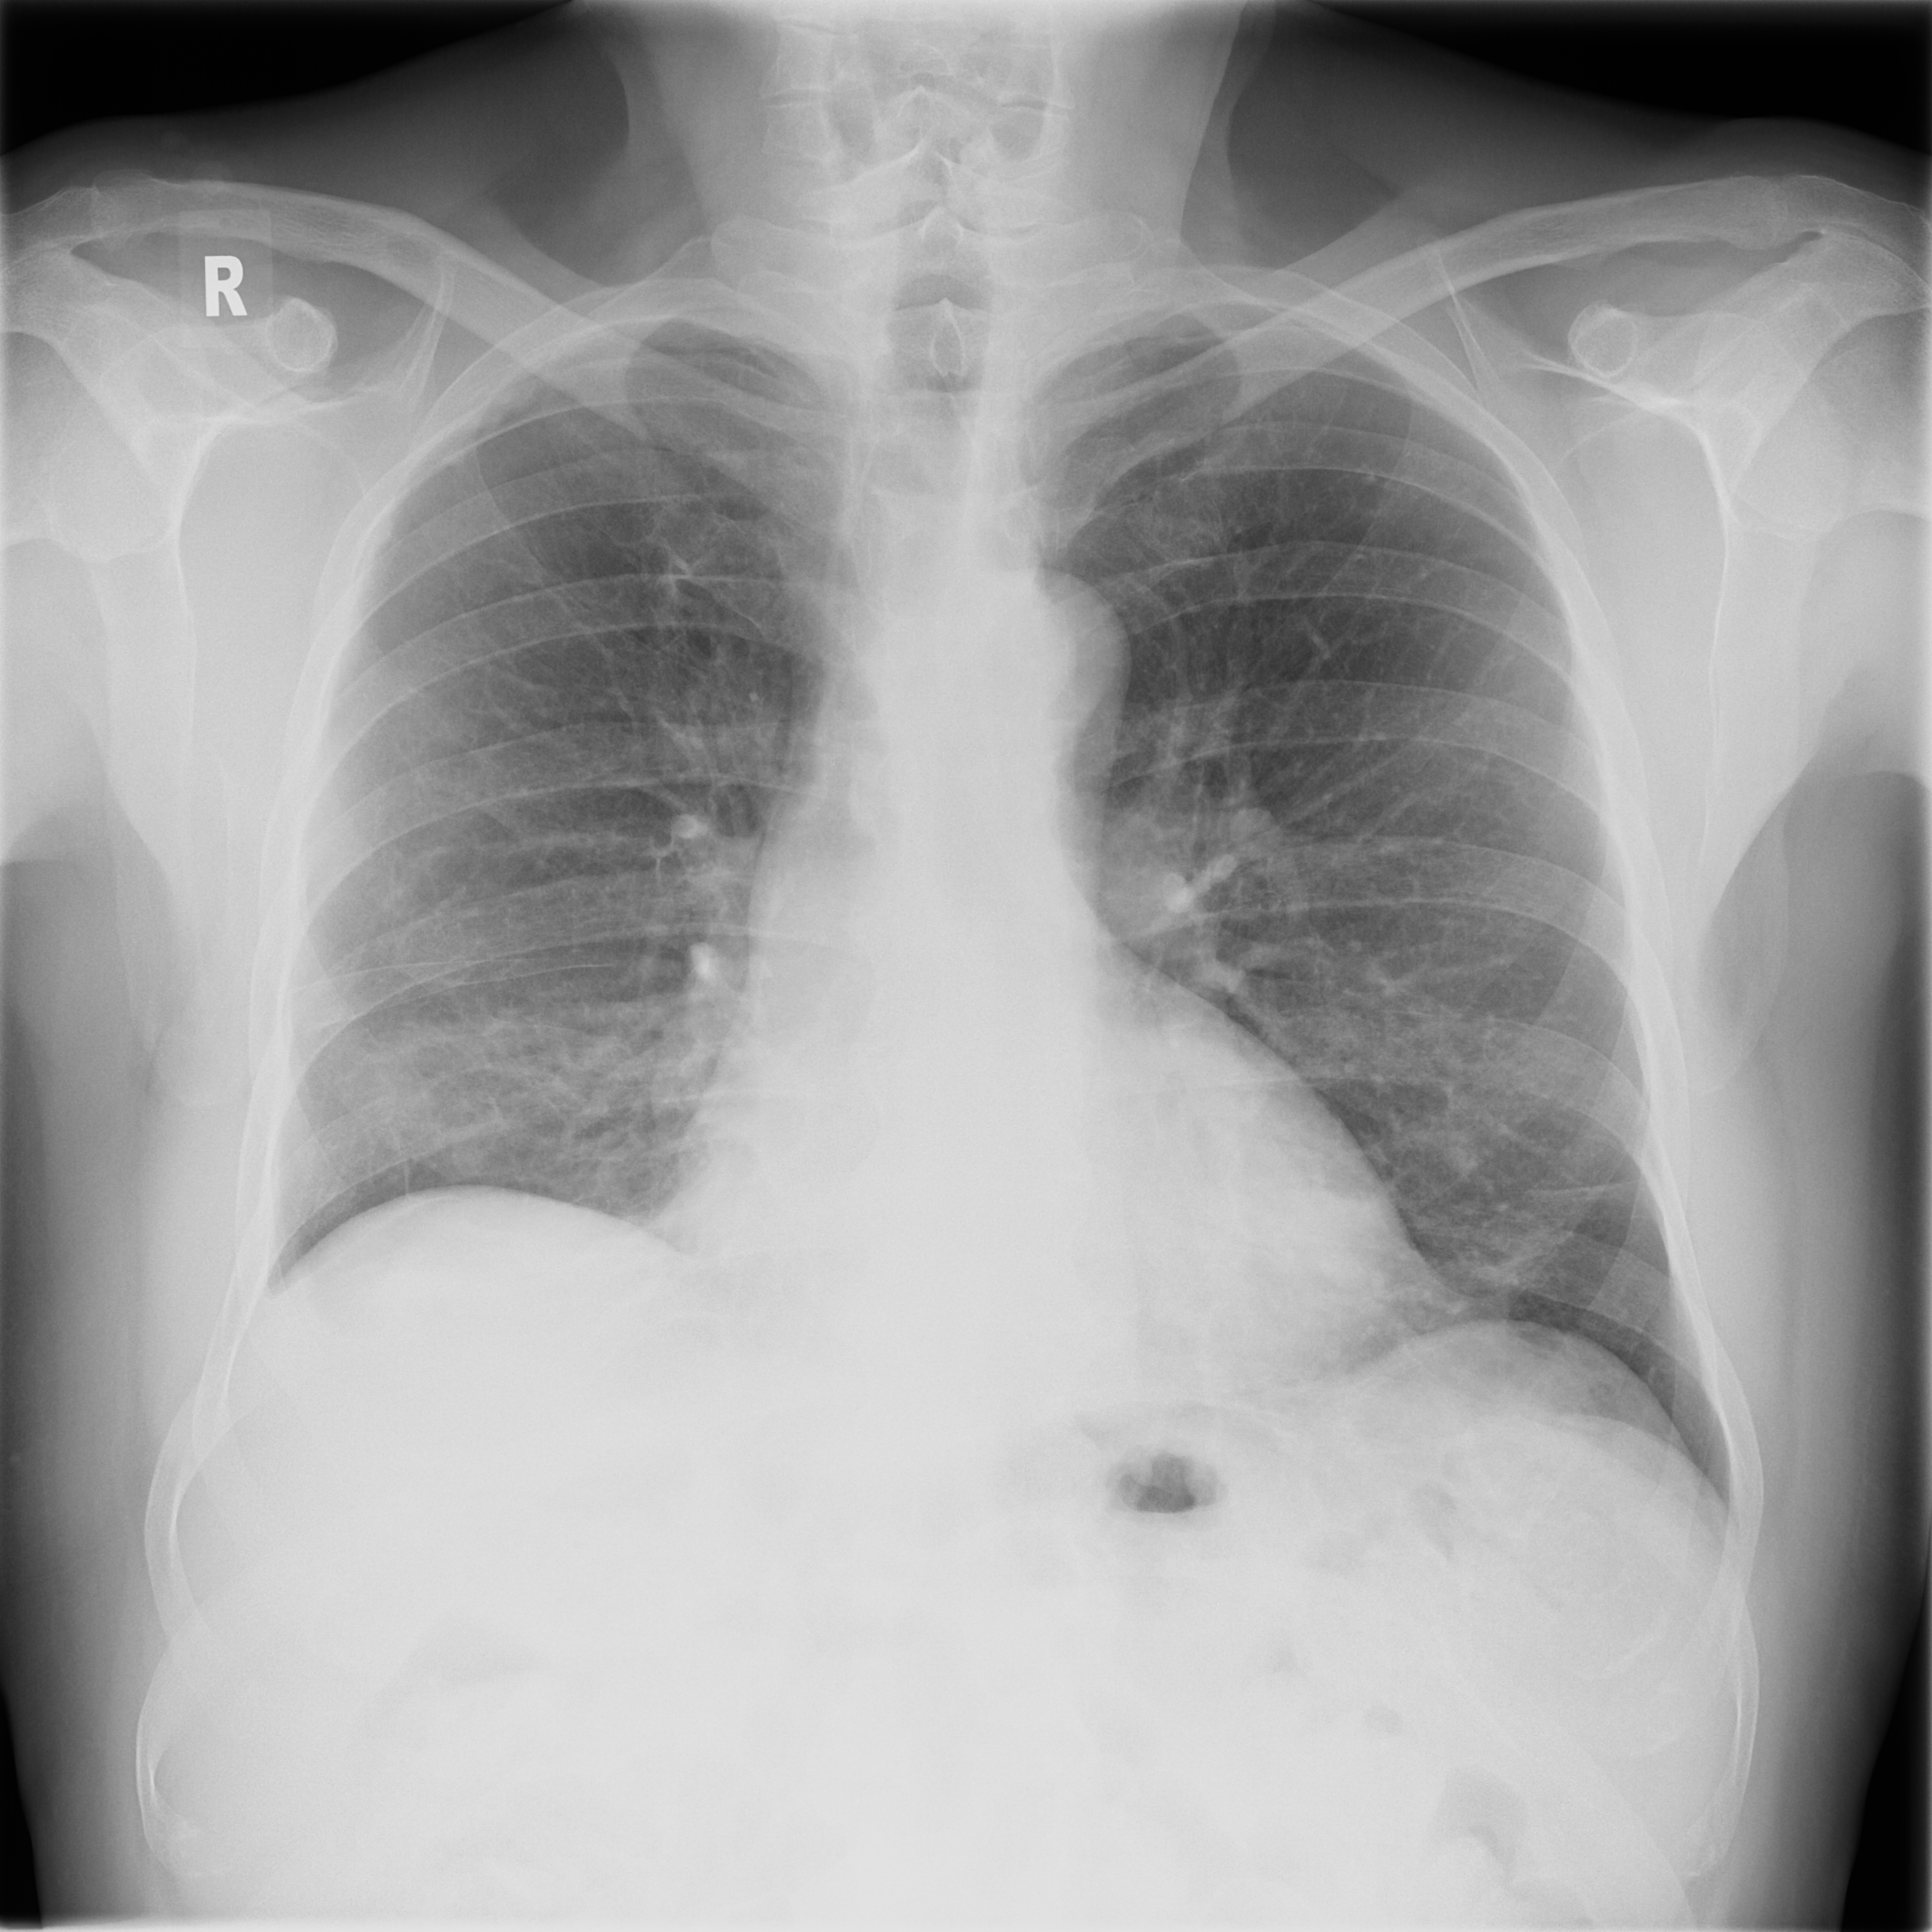

3.1.3 Example 2: data driven reconstruction methods in lung CT screening

There is sufficient evidence that screening for certain tumours using CT images may improve prognosis of cancer survivability (citep \@BBN(Boiselle, 2013)). As mentioned above, in order to gain better image quality with less X-ray dose, many enhanced regularization techniques with integrated machine learning steps have been suggested for CT reconstruction, and in a full reference setting they are commonly evaluated by applying PSNR and SSIM, see e.g. (citep \@BBN(Adler and Öktem, 2018; Hendriksen, Pelt, and Batenburg, 2020; Unal, Ertas, and Yildirim, 2021)). As CT images are generally taken to perform a clinical task, they are not the final step of a medical process but often the initial one. Therefore the definition of what makes a good image heavily depends on the task in hand, and for prognosis related cancer the identification of tumours is of upmost importance.

In on-going research on photon counting detector types and screening procedures for lung cancer (EPSCR grant: EP/W004445/1) an experiment was conducted testing enhanced reconstruction algorithms. Simulations using less than 10% of a clinical X-ray dose were performed to investigate if data-driven methods could sufficiently enhance the images to clearly see the tumours in the lungs while providing very low amount of dosage to the patients. The corresponding data was a CT-dose simulation, using images from the open LIDC-IDRI dataset (citep \@BBN(Armato et al., 2011)) as references, as well as simulated and reconstructed images with in-house software. Figure 3 shows the results of the experiment. We show the reference image used as basis for the simulation, together with five different reconstruction algorithms. The first is an iterative solver, a gradient descend algorithm with TV minimization (citep \@BBN(Sidky et al., 2012)) and (c)-(f) correspond to machine learning methods: FBPConvnet is a denoising algorithm that cleans the bad image (citep \@BBN(Jin et al., 2017)), LPD is an iterative unrolled method that combines traditional solvers with machine learning (citep \@BBN(Adler and Öktem, 2018)), Noise2Inverse is a self-supervised learning method (i.e. does not require ground truth data) (citep \@BBN(Hendriksen et al., 2020)) and ItNet is another iterative unrolled method, the best performing winner of the AAPM DL-Sparse-View CT challenge (citep \@BBN(Genzel, Macdonald, and März, 2021)). ItNet is also judged here as the best result according to PSNR, SSIM and LPIPS.

Refer to caption

(a) Reference

(b) (27.6, 0.70, 0.37)

(c) (31.9, 0.73, 0.29)

(d) (32.5, 0.84, 0.19)

(e) (32.5,0.77, 0.20)

(f) (33.0, 0.89, 0.12)

Figure 3: Reference image (a) and outputs of different reconstruction methods (b)-(f) applied to dose simulated data. PSNR/SSIM/LPIPS are unable to identify the best reconstruction (c), where also the tumour is visualized well.

FR-IQA mismatches

This experiment was performed to evaluate the quality of different kinds of CT reconstruction, and especially the lung tumour detection capabilities thereof. The best result according to the chosen IQA measures is given by ItNet in Figure 3(f), which performs visually poorly. Not only the tumour (zoomed in white circle) is significantly less visible in the reconstruction, but ItNet also produces structures in the lung that are different than the ones in the reference image; it blurs and lengthens much of the soft tissue present in the lungs and it also created structure from noise in some places. Moreover, the image is overly smooth. Comparing the other reconstruction algorithms, it seems that FBPConvnet Figure 3(c) is the one performing best at preserving the shape of the lung nodule, even when the resulting image contains enhanced pixel-level noise.

We can see here that the qualitative findings strongly contradict the numbers provided by the selected measures. The reconstruction of ItNet, Figure 3(f), is outperforming the other reconstructions in regards of the measures, and the qualitative winner FBPConvnet, Figure 3(c), is judged as second worst by the same measures. This experiment suggests that the discussed measures are not a good choice for that kind of CT reconstruction applications and are yielding misleading results.

While pixel-independent random noise may be a worse effect in a natural image than a slightly oversmooth reconstruction, this is not true in CT images, where small structures may disappear if smoothing is promoted against edge preservation. In iterative reconstruction algorithms such choices are explicitly made by choosing the prior appropriately, in data-driven models the researcher has limited control on the type of implicit priors the algorithm learns from the data, i.e. model builders do not know what the algorithms chooses to learn from the ground truth. In these cases appropriate evaluation would therefore be even more important to ensure quality. If this is followed by a blind evaluation using non-appropriate metrics, the promotion of less desirable images can happen, chosen by an implicit assumption on the metric rather than the actual goal of the task.